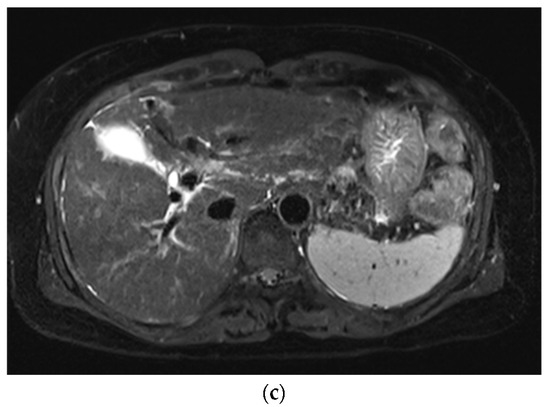

Improved Single Breath-Hold SSFSE Sequence for Liver MRI Based on Compressed Sensing: Evaluation of Image Quality Compared with Conventional T2-Weighted Sequences

3. Results

3.1. Subjective Image Quality

3.2. Lesion Assessment